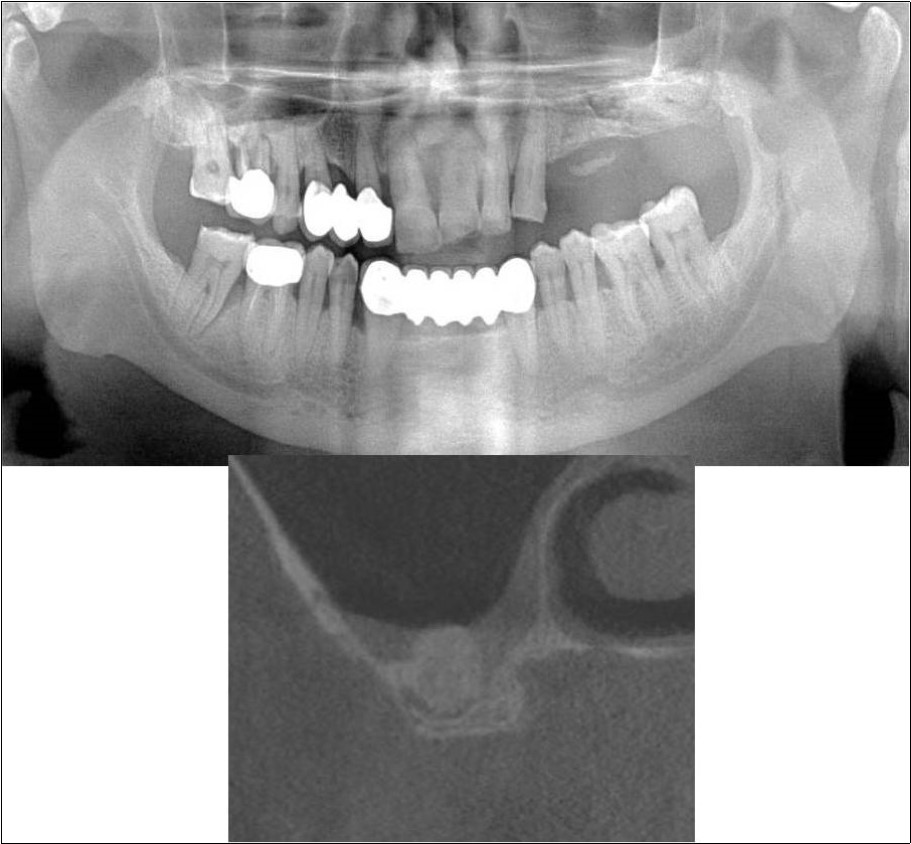

A 25 years old young male patient reported to the Department of Oral and Maxillofacial Surgery, D.A.P.M.R.V Dental College and Hospital seeking options for implant supported prosthesis for rehabilitation of missing right first molar. The tooth was extracted 6 months ago because of gross loss of tooth structure and poor prognosis for root canal treatment. Patient did not give history of any existing sinus pathologies. All possible rehabilitative options were explained to the patient and a treatment plan of replacement of missing tooth with implant supported prosthesis was finalized.

Clinical and Radiological Assessment:

1.Partially edentulous maxillary arch with missing 16;

2.Increased pneumatisation of right and left maxillary sinus;

3.Height of available bone- 1.8mm;

4.Transverse thickness of available bone (CBCT evaluation)- 6.2mm;

5.Implant supported prosthesis i.r.t 35 and 36;

6.Fixed partial denture i.r.t 45, 46, 47;

7.Inter-ridge space adequate to place implant (12mm).

Treatment:

Patient underwent the procedure of direct sinus elevation using sinus lateral approach kit. After crestal and vertical release incisions, muco-periosteal flap was raised to expose the buttress region. A bony window of 1cm diameter was created; sinus lining identified and elevated up to receive calcium phosphosilicate as graft material and closure was achieved under local anaesthesia and strict aseptic protocols. Implant placement was planned to be carried-out after a period of 6 months to allow for the consolidation for graft and naive bone formation. At the end of 6 months, a repeat CBCT scan was advised to evaluate the increase in bone height. (Figure 17a,b, pre-treatment; Figure 18a,b, post-treatment)

Figure 17.a,b. Pre-treatment OPG and cross section of CBCT showing residual alveolar bone height for Case No.6;

Figure 18.(a,b) Post-treatment OPG and cross section of CBCT showing residual alveolar bone height for Case No.6;